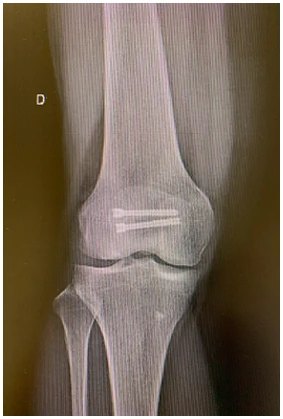

As osteotomias são procedimentos cirúrgicos que envolvem o corte e reposicionamento dos ossos ao redor da articulação do joelho para corrigir deformidades angulares, como a osteoartrose em estágio inicial ou instabilidade ligamentar. Esse procedimento visa redistribuir as forças na articulação do joelho e aliviar a pressão sobre as áreas danificadas da cartilagem.